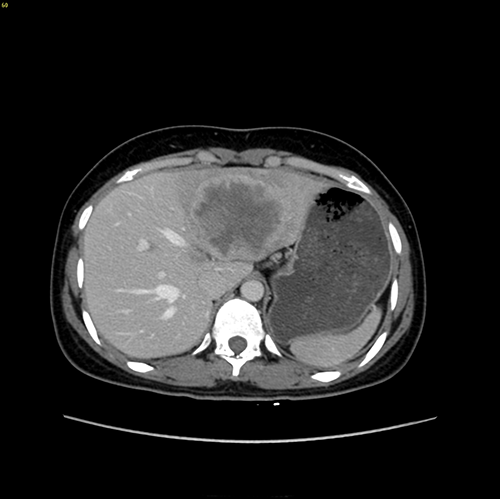

左肝肝癌---扩大左半肝切除+尾状叶切除